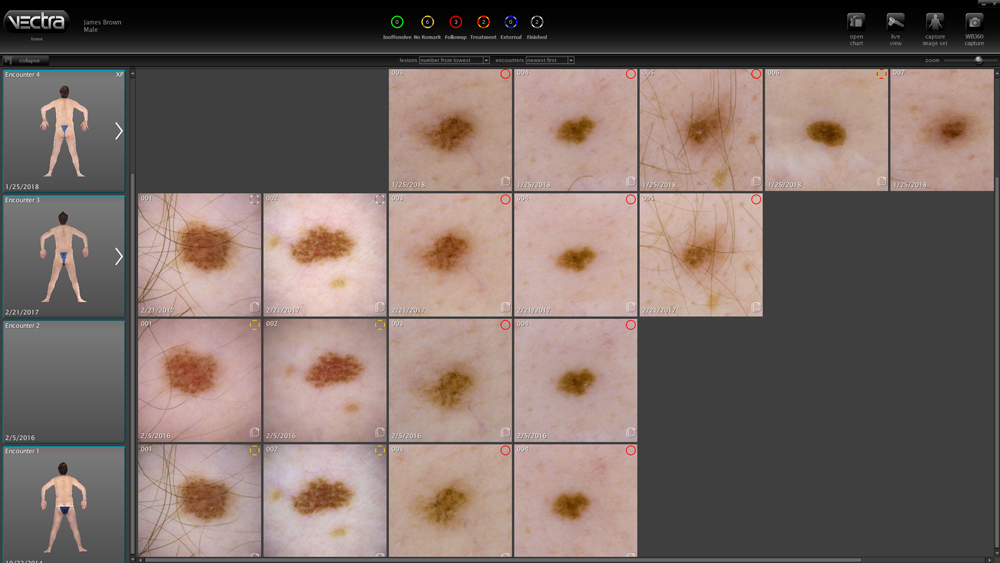

Designed specifically for dermatology, the VECTRA WB360 whole body 3D imaging system captures the entire skin surface in macro quality resolution with a single capture. The fully integrated software allows clinicians to map and monitor pigmented lesions and distributed diseases of the skin. Other applications include documenting psoriasis and vitiligo.